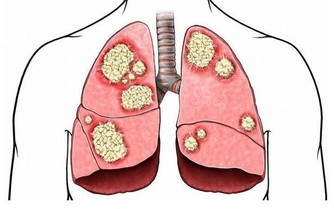

1.促進肝解毒、腎排毒

在高抬腳時,血液會迅速流回肝、腎,給予重新解毒、排毒。

高抬腳時新陳代謝增加,腰部以下會有強烈極酸的反應,為了排解瞬間增加毒素,人體腦下垂體自會分泌激素,激發潛能,加強排毒。